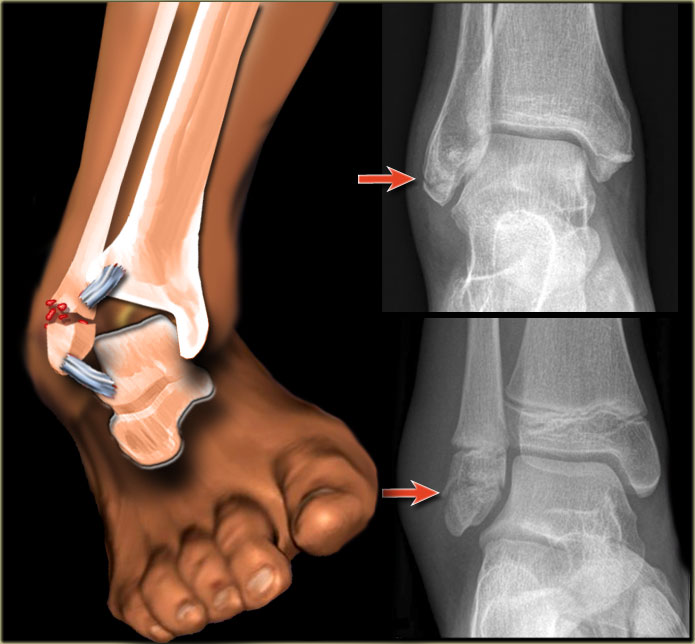

Treatment of an ankle largely depends on the type and severity of the fracture. If there is an open fracture, a tetanus shot needs to be given. Following this, a disgnosis of what exact type of fracture needs to be made. This involves examination of the leg clinically and radiographically. Neurological testing will also be performed to determine if there is damage to the nerves and blood vessels. Following this, the course will largely depend on the extent of the ankle fracture and whether it is an open fracture. Patients usually need operative fixation or repair of ankle fractures. Subsequently, expect six to eight weeks in immobilization with a cast, and expect to be nonweightbearing on crutches. Following this, physical therapy is quite useful in regaining complete function of the afflicted ankle. Physical therapy is effective in helping patients regain full mobility and range of motion.